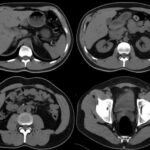

Fig. 7. TC post operatoria.

Paciente de sexo masculino de 40 años de edad, diabético tipo 1, sin hemodiálisis. Presentó una tomografía preoperatoria sin calcificaciones en la pared del sistema vascular (Fig. 6). El paciente manifestó dolor abdominal y presentó fiebre posterior al acto quirúrgico, lo cual determinó la realización de una TCMD con contraste EV (Fig. 7). Los niveles de laboratorio post operatorio de glucemia, lipasa y amilasa fueron: 148mg/dl, 37 U/L y 150 U/L, respectivamente.

En el caso Nº 2, las imágenes mostraron trasplante pancreático en fosa iliaca y flanco derecho, con permeabilidad de las arterias mesentéricas pancreáticas, anastomosadas sin alteraciones a nivel de la arteria iliaca derecha y sin cambios significativos ni defectos de relleno de las estructuras venosas. Tampoco se observaron alteraciones en el asa duodenal interpuesta entre la vejiga y el neopáncreas.

Sin embargo, a pesar de la aparente normalidad del estudio tomográfico realizado, la evolución del paciente fue tórpida, con dolor abdominal muy agudo y cuadros febriles, por lo que fue reintervenido quirúrgicamente, realizándose resección de la cabeza del páncreas por necrosis y fístula. Se diagnosticó pancreatitis por punción y biopsia.

En la segunda tomografía control efectuada se evidenció una disminución en el calibre de la anastomosis arterial, lo que se correlacionó con vasculitis. Con posterioridad a las complicaciones descritas, el paciente presentó los siguientes niveles de laboratorio: glucemia de 88 mg/dl y creatinina de 1.34 mg/dl.